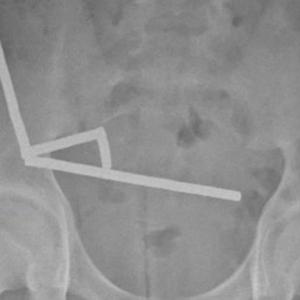

В конкретния скорошен случай 25-годишна жена отива в спешното на болница в Чандигар, Индия с кървави сълзи на лице. Това е вторият път, в който проявява този симптом, като първоначалната му поява е била преди месец. И в двата случая – кървавите сълзи се появяват, докато е в менструация.

Източник: BMJ Case Reports 2021.

Лекарите извършват множество тестове, за да установят причината. Резултатите от всички са нормални. По очите не са открити наранявания, никой от семейството не страда от това състояние, а кръвоносните съдове в конюктивата не са подути или пълни с кръв. Гинеколог и специалист уши, нос, гърло също я преглеждат и не откриват нищо. Жената е хемодинамично стабилна с нормално очно налягане. Не е открито кървене от която и да е друга област в тялото, а тестовете за крехкост са отрицателни, а нивата на факторите, свързани с кръвосъсирването, са нормални. Конюнктивалната проба също е нормална – не са открити анормални клетки.